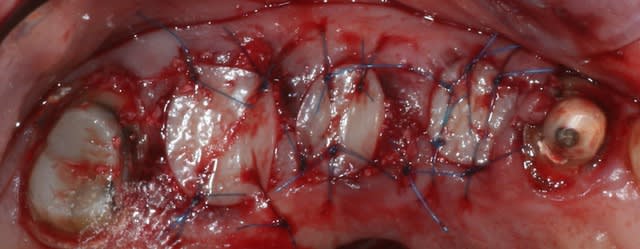

bon finalement 8 mm c'était suffisant.

Img 9010 tehnsv - Eugenol

magnifique mac, tu vas nous faire suivre ce cas step by step.

bon , une question: caractéristiques du fil que tu as utilisé ici ?

sur les conseils d'olivier noah, c'est du prolene 6.0.

Et quel bistouri circulaire as-tu utilisé?

ceux conseillés par vava en 6 et en 8 mm, les mêmes chez astra c'est 12 euros pièce et y en a pas en 8mm.